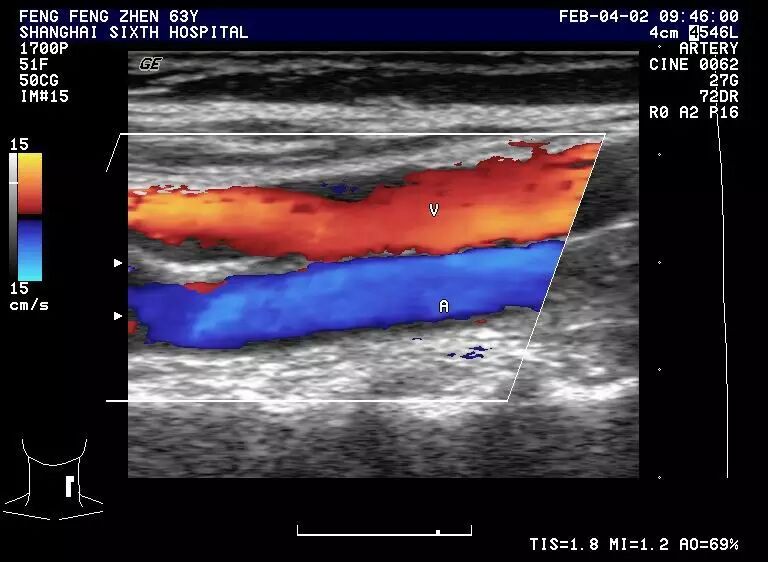

彩色多普勒    正常颈动脉血流为层流,呈红迎蓝离之血流色彩,管腔中为色彩明亮的高速血流,靠近管壁处色彩略暗淡。

1.4 正常颈动静脉血流图